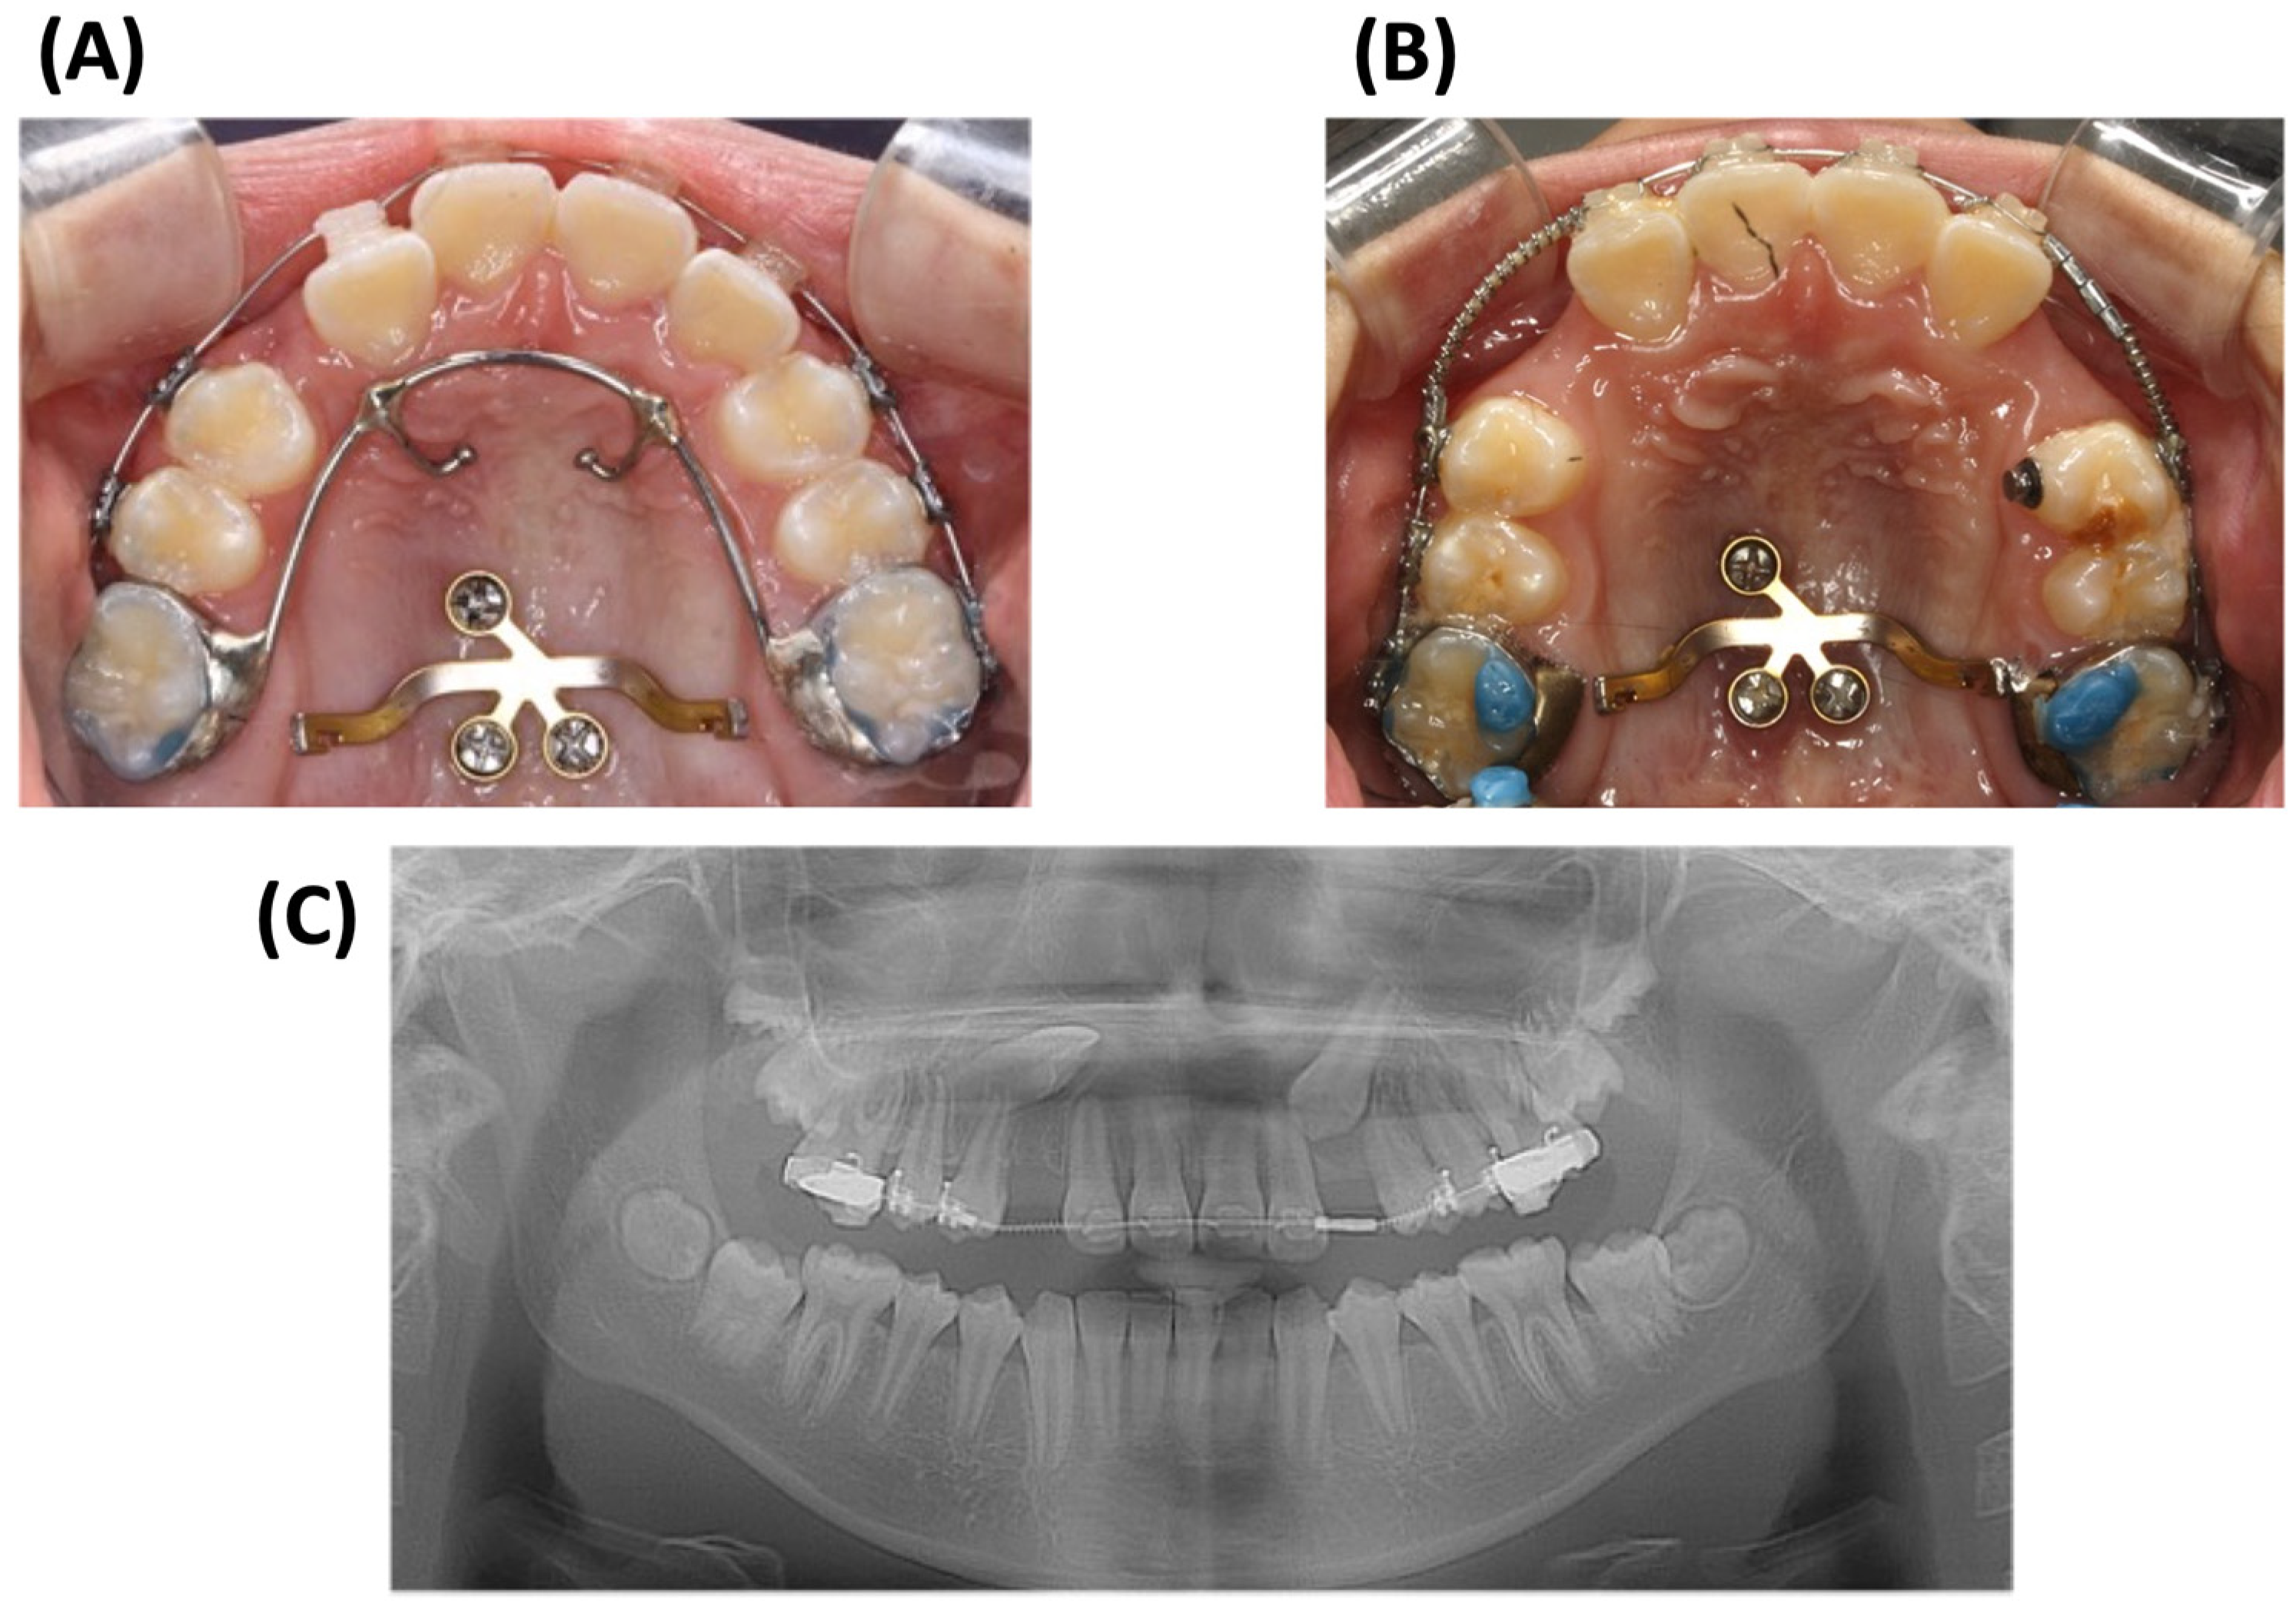

2.4. Treatment Progress